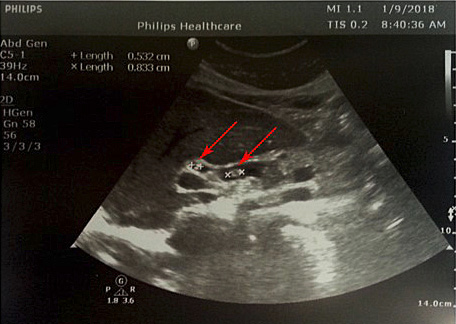

4 pav. ERC vaizdas: askaridės šešėlis BTL (pažymėta rodyklėmis)

Pacientei įtarta pilvo skausmų priežastis – tulžies latakų akmenligė, nesant mechaninės geltos. Priimtas sprendimas atlikti duodenoskopiją ir ERC tyrimą. Duodenoskopijos metu įvertinta, kad papilla Vateri yra po PST procedūros. Kontrastavus BTL, pastebėtas >5 cm ilgio 4 mm skersmens prisipildymo defektas lygiais kontūrais. Naudojant Dormia krepšelį, iš tulžies latako pašalintas prisipildymo defektas – askaridė (3–5 pav.). Atlikus procedūrą, pacientės sveikatos būklė pagerėjo, pilvo skausmas regresavo, nesikartojo. Papildomai atlikta dehelmintizacija mebendazolu, antihelmintiniu vaistiniu preparatu („Vermox“).

Sergant tulžies latakų askaridoze, kraujo tyrimai gali atitikti normos ribas. Tokiu atveju įtarti patologiją padeda paciento nusiskundimai, išsami ligos ir gyvenimo anamnezė (kelionės, namų aplinka, valgymo įpročiai ir sąlytis su dirvožemiu). Specifinių (ligą diagnozuojančių) laboratorinių tyrimų askaridozei nustatyti nėra. Tiksliai diagnozuoti parazitų invaziją į žarnyną, kai laboratoriniai tyrimai nepatologiniai, galima identifikavus askaridžių kiaušinėlius paciento išmatose [3, 27]. Kirmėlių migraciją į tulžies latakus galima nustatyti atlikus ultragarsinį tyrimą. Dažnai ultragarsu pastebimas prisipildymo defektas BTL. Jis būna pailgos arba cirkuliarios formos, be tulžies latakų akmenims būdingo šešėlio – artefakto. Dėl šios priežasties ultragarsu stebimas prisipildymo defektas dar vadinamas „minkštu“ radiniu (1, 2 pav.). Nors ultragarsinis tyrimas vertinamas kaip jautrus ir specifiškas (atitinkamai 40–70 proc. ir 90 proc.), tyrimo kokybė priklauso ir nuo tyrėjo patirties. Tulžies latakuose esant oro po buvusių intervencijų arba kirmėlių maceracijos metu, kai kirmėlė negyva, ji gali būti nepastebėta [2, 3].

Tulžies latakų patologijai diagnozuoti taip pat naudojama magnetinio rezonanso cholangiografija ir ERC. Šie tyrimai iš esmės skirtingi, tačiau jų jautrumas ir specifiškumas tulžies latakų obstrukcijos priežasčiai nustatyti siekia beveik 100 proc. Minėti tyrimai taip pat padeda diferencijuoti patologiją – nustatyti kitas gretutines kepenų, tulžies latakų, kasos ligas, onkologinį procesą. Kompiuterinės tomografijos jautrumas ir specifiškumas patologijos atveju yra atitinkamai 54–70 proc. ir 80–90 proc. [3, 28, 29]. Retesniais atvejais nustatyti kirmėles dvylikapirštėje žarnoje galima atlikus diagnostinę gastroduodenoskopiją.